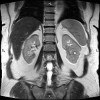

MRI of the retroperitoneal space.

МРТ забрюшинного пространства. Метод инструментальной визуализации, в основе которого лежит программный анализ взаимодействия магнитных волн с ядрами атомов водорода внутренних органов и окружающих мягких тканей. В ретроперитонеальном пространстве расположены органы, не покрытые брюшиной (почки, мочеточники, надпочечники), частично покрытые брюшиной (поджелудочная железа и 12-перстная кишка), магистральные сосуды (аорта, нижняя полая вена), околопочечная клетчатка и лимфоузлы. В этих органах могут развиваться различные структурные аномалии и заболевания, которые могут быть выявлены с помощью МРТ. К числу таких патологических процессов относятся пороки развития, сосудистые, воспалительные, опухолевые ( метастатические) заболевания. МРТ забрюшинного пространства используется для контроля результатов оперативного вмешательства, лучевой терапии, ПХТ.